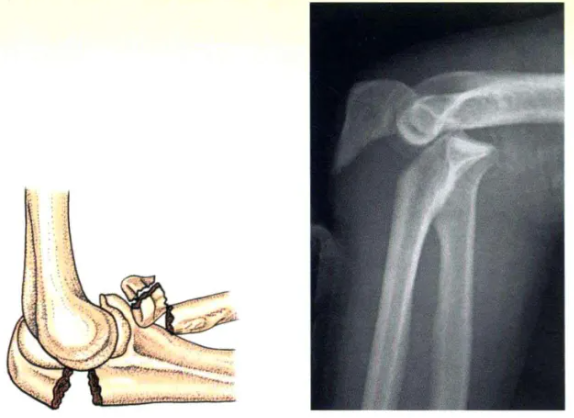

F型(xing):骨折-脫位型(xing)

F型(xing):顯著不穩定的(de)復(fu)雜(za)骨折需要注(zhu)意(yi)所有損傷的(de)骨性和軟(ruan)組織成分